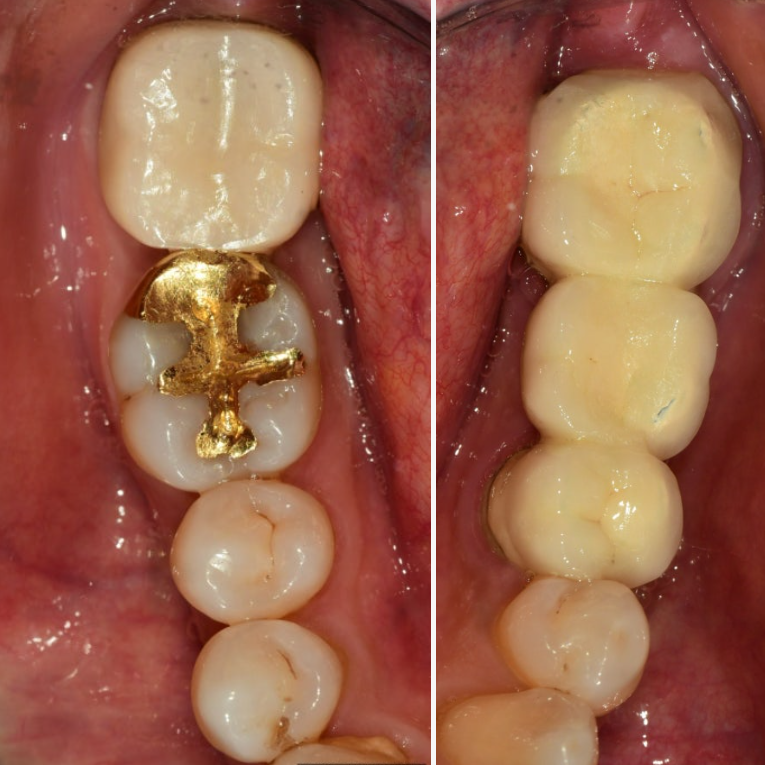

브릿지를 제거하고 어금니를 살펴보니 2차 우식이 진행되어 치아가 상당히 많이 연화되었고 치수강까지 진행되어 근관치료(신경치료)를 진행하기로 하였습니다.

맞춤형 지대주 연결 및 PMMA 임시치아 부착.

작은 어금니, 어금니는 최종 지르코니아 보철물 부착.

크라운 제거 후 사진

두 번째 어금니는 우식이 진행되어 치료가 필요한 것으로 보입니다.